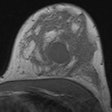

EJR: MRI measures up in estimating breast cancer tumors